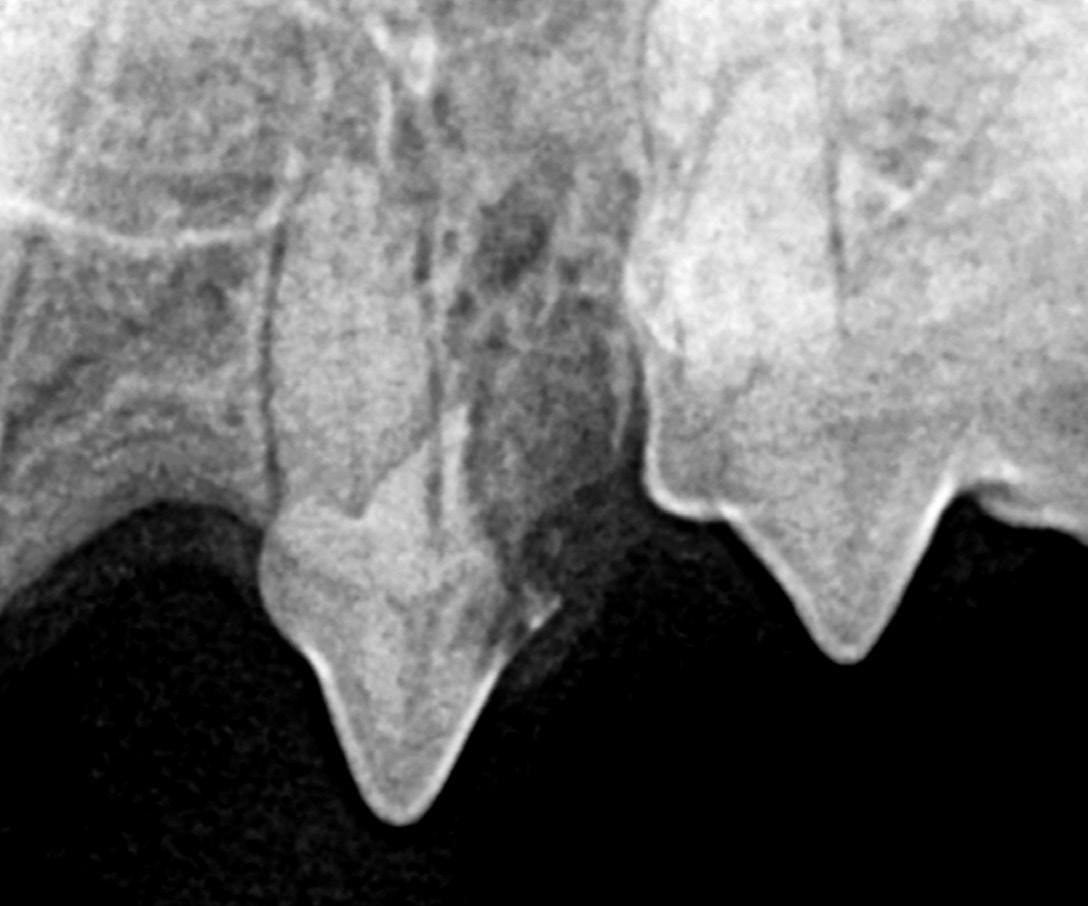

• Abnormalities in the root canal, such as obstruction, resorption, or enlarged canal(s) compared to adjacent teeth.

• Periapical pathology, such as widened periodontal ligament space at the tooth's apex and circumscribed alveolar bone resorption. In the early stages of endodontic disease, bony changes are not radiographically present. As the infection progresses, a homogeneous radiolucency at the apex or a dark halo in the periapical tissues becomes apparent, typical of an infection. A sharply outlined circumscribed radiolucent area is commonly caused by a periapical cyst, which usually arises from preexisting granulomas.

Figure 6: Right maxillary second incisor enlarged root canal and periapical lucency consistent with endodontic disease. Image courtesy of Dr. Jan Bellows. Figure 7A: Fractured left mandibular canine with pulp exposure and periapical lucency. Figure 7B: Periapical lucencies surrounding the three roots of the right maxillary fourth premolar. Figure 7C: Pulp exposure and periapical lucencies consistent with apical granulomas affecting a dog’s left mandibular first molar. Image courtesy of Dr. Jan Bellows.